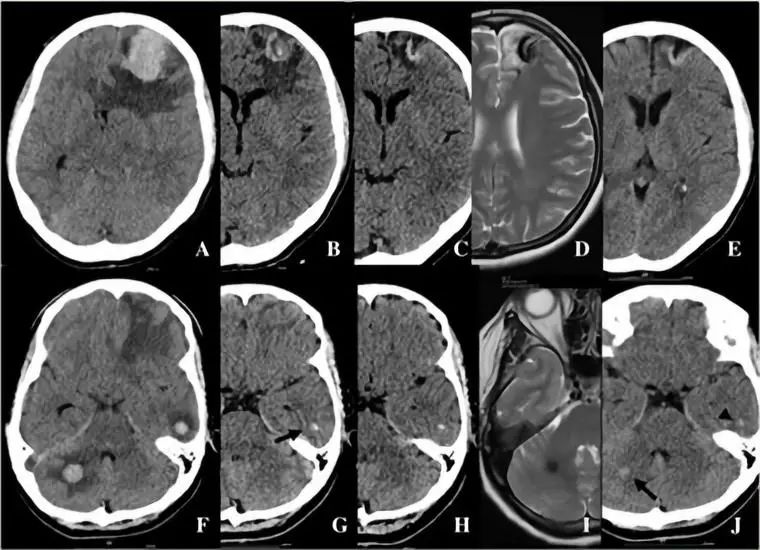

脑血管畸形

1. 脑AVM

2. Sturge-Weber综合征

2. 结节性硬化

结节性硬化临床表现以皮脂腺瘤、癫痫和智力低下三联症为特征。病理特点为错构瘤,以室管膜下多发结节状钙化为主要特征性改变。

4. 神经纤维瘤病

神经纤维瘤病患者大脑半球及小脑半球表面也可钙化,少数情况下钙化发生在室管膜下及基底节。下图是一例NF-2患者的头CT。